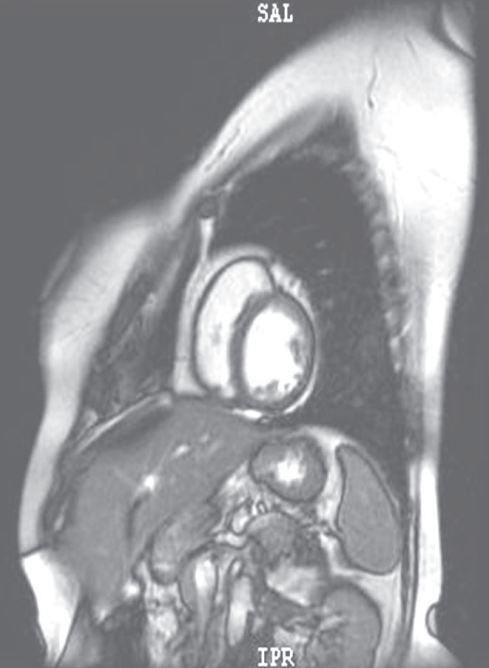

摘要:關(guān)于擴張性心肌病的最新治療,小巷深處的隱藏寶藏正逐漸為人們所發(fā)現(xiàn)。通過先進的醫(yī)療技術(shù)和方法,擴張性心肌病的治療取得了新的進展。這些治療方法旨在改善心臟功能,提高患者生活質(zhì)量。小巷深處的醫(yī)療機構(gòu)或?qū)<铱赡茈[藏著寶貴的治療經(jīng)驗和方法,為尋求最佳治療方案的病患帶來希望。更多詳細信息需要進一步探索和研究。

擴張性心肌病是一種嚴重的心臟疾病,但“心之港灣”為你帶來希望,這里的專家團隊一直在深入研究擴張性心肌病的最新治療方法,并深知每位患者都渴望得到最佳的治療和關(guān)懷,他們努力不懈,為患者帶來生機和新生。